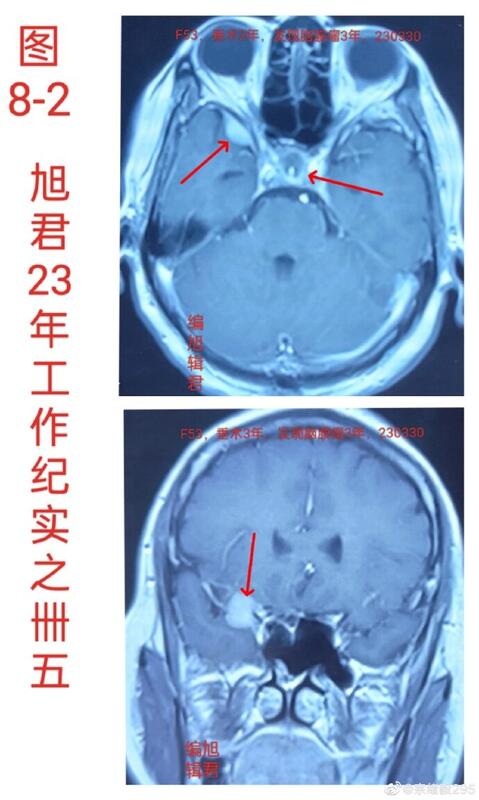

图8,1-2,某患者53岁,垂体瘤术后三年,术后三个月复查,发现右蝶骨嵴小脑膜瘤,复查无变化。

图8-2